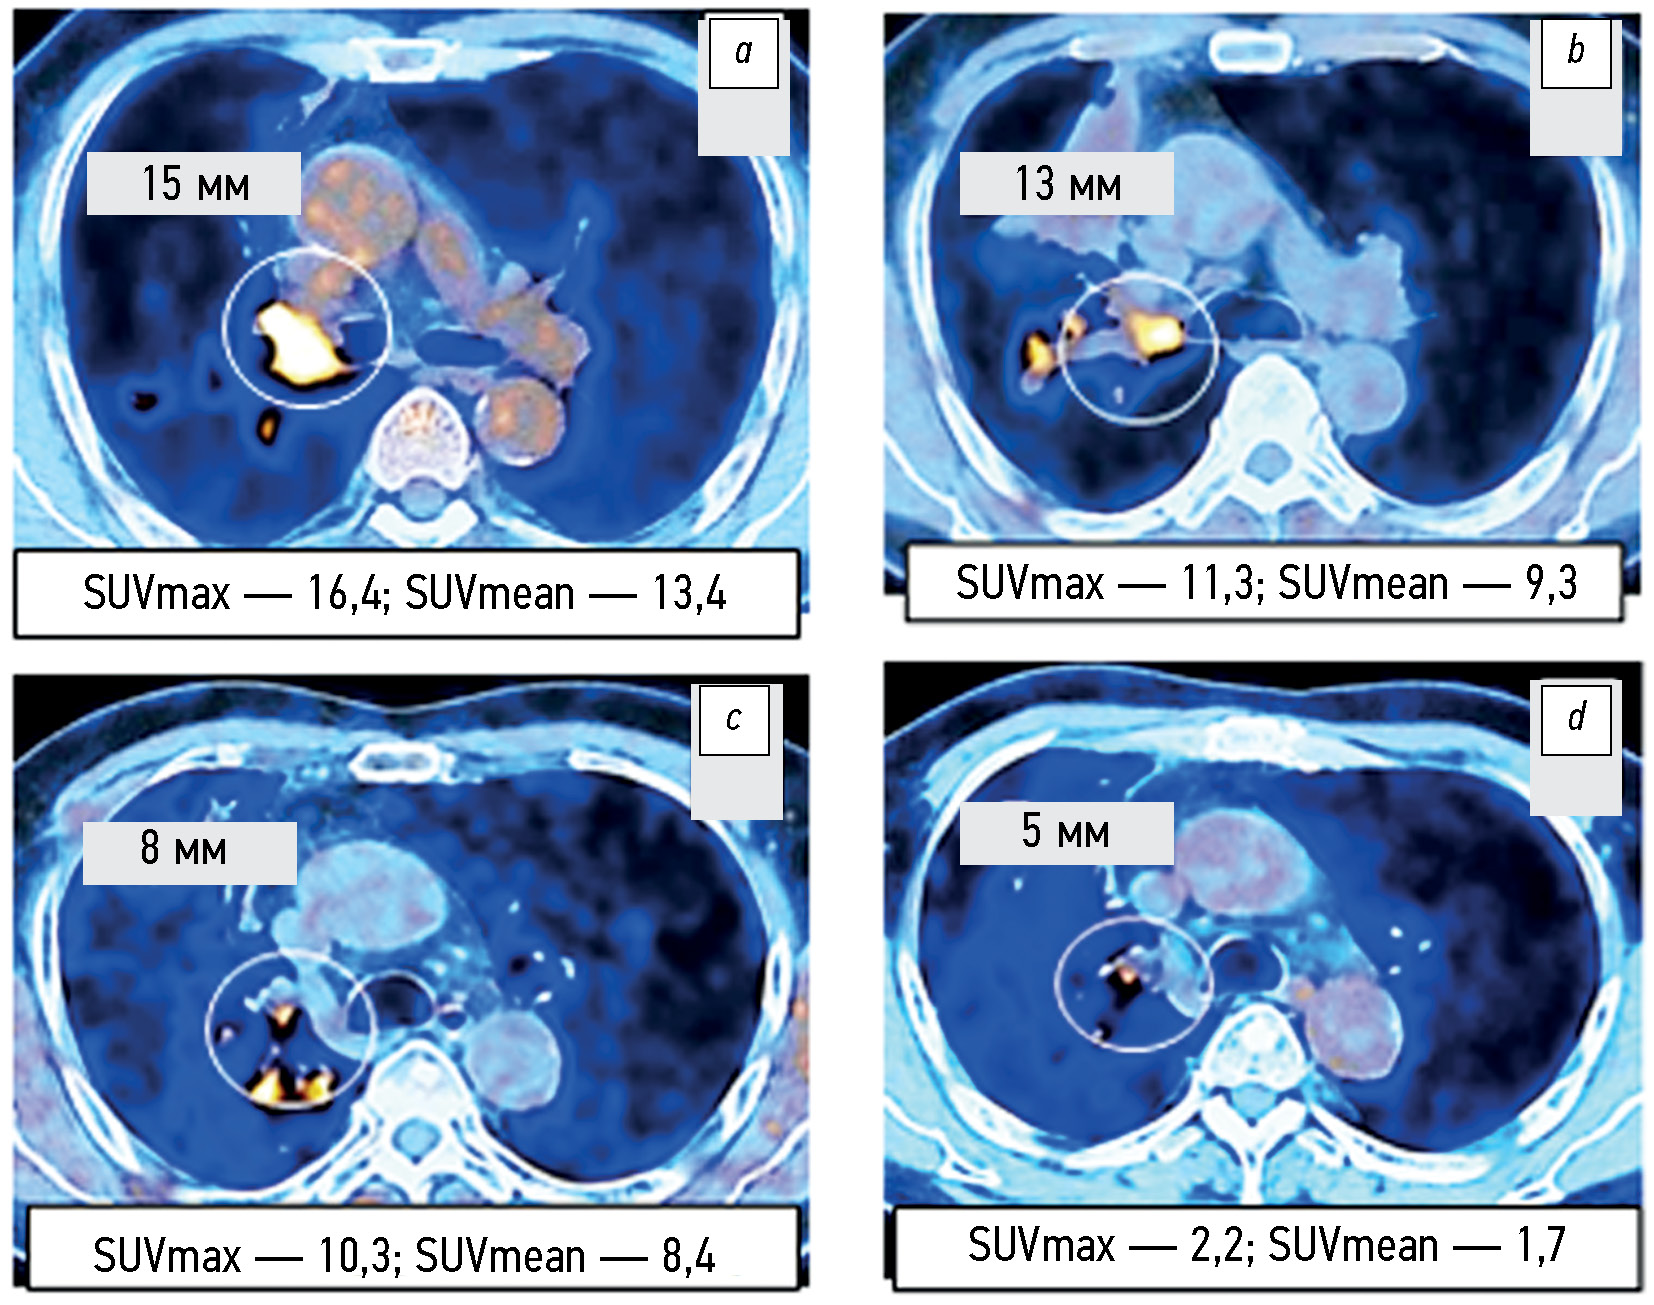

目的 — 研究使用RECIST1.1标准和代谢指数SUVmax和 SUVmean的变化比较评估非小细胞肺癌和EGFR基因突变患者对酪氨酸激酶抑制剂靶向单药治疗和联合治疗肿瘤反应的可能性。

材料和方法。分析了2019年至2022年期间105名非小细胞肺癌患者的18F-氟脱氧葡萄糖(18F-FDG)正电子发射和计算机断层扫描相结合的研究方案,其中包括75名EGFR基因活化突变的患者。辐射负载因人而异,范围为45至90mSv。18F-FDG放射性药物的容积活性为260-500MBq。 评估了治疗前和治疗开始后1.5-2.0个月内最大靶灶直径总和以及代谢指数SUVmax和 SUVmean的变化。在17名非小细胞肺癌患者中,正电子发射断层扫描和计算机断层扫描相结合变化的观察持续时间至少为12个月。

结果。根据接受酪氨酸激酶抑制剂贝伐单抗或贝化疗结合综合治疗的第2组和第3组EGFR基因突变非小细胞肺癌患者的正电子发射和计算机断层扫描相结合的数据和代谢指数SUVmax和SUVmean的变化,发现疾病进展的频率(P=0.043和P=0.029)明显低于第1组患者和对照组(4.2% vs 20.0-21.8%)。部分治疗反应(P=0.092)检测率较高的趋势(58.3% vs 40.0%)也不明显。 治疗早期最大靶灶直径之和的类似变化在统计学上并不显著(p=0.187)。研究表明,在对部分非小细胞肺癌患者的长期观察中,至少有50%的病例中,最大直径总和的变化重复了第一次对照研究中发现的SUVmax和SUVmean的相应变化。

结论。根据正电子发射和计算机断层扫描相结合的数据和代谢指数SUVmax和SUVmean的变化表明,对照组患者酪氨酸激酶抑制剂贝伐珠单抗或化疗的单药靶向结合的综合治疗早期反应,与酪氨酸激酶抑制剂靶向单药治疗或化疗的反应相比,尽管根据RECIST1.1标准靶灶最大直径的变化趋势无统计意义,但疾病代谢进展的频率明显降低。至少有50%的病例在治疗早期代谢指数SUVmax和SUVmean的变化超过了靶向病灶最大直径总和的类似变化,根据 RECIST1.1标准,这些变化可用于及时识别有进一步发展的高风险患者群体。